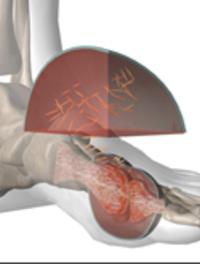

La goutte est une arthrite inflammatoire des plus communes. Elle se caractérise par des accès articulaires induits par les cristaux [...]

La goutte est une maladie fréquente dont la prise en charge reste largement insuffisante. Moins de la moitié des patients reçoivent [...]

Le traitement de la crise de goutte repose sur la colchicine et de plus en plus sur les anti-inflammatoires non stéroïdiens (AINS). [...]